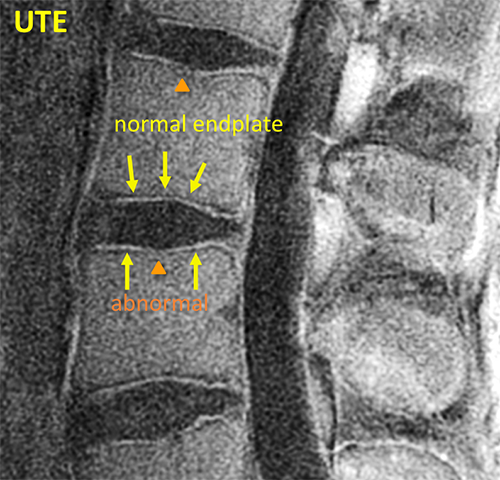

Spine UTE

UTE MRI reveals the structure of cartilage endplates with high contrast. Both normal and abnormal structures could be discerned here.